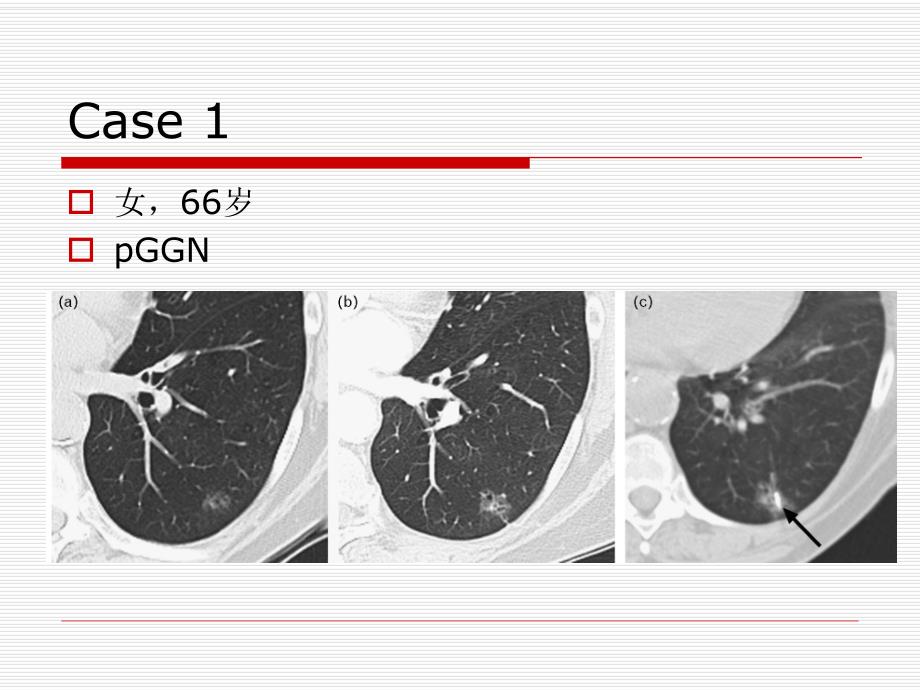

1、肺结节肺结节CT随访策略随访策略Case 1o 女,66岁o pGGNCase 2Case 3肺结节(pulmonary nodule)o 定义:指肺实质内单发或多发的圆形或类圆形、直径3 cm,不伴有肺不张、无淋巴结肿大或肺内其他异常的病变分类o 纯磨玻璃密度(pGGN,pGGO)o 混合性结节(partial solid GGN)o 实性结节(Solid Nodule)实性结节实性结节无肺癌危险因素排除吸烟史;年龄60岁;有肺癌史或肺外其他癌病史o 4mm,无须随访,但患者必须完全知情随访的利与弊o 4 mm-6 mm,隔12个月随访1次,若无变化无需随访o 6 mm-8 mm,612、1

4、描技术o 高分辨o 低剂量(80mA)o 薄层(2.5mm)良性结节男,39岁;a-GGN,b-3个月后随访肺腺癌女,59岁;a-GGN,b-5个月后随访,c-9个月后随访;有卵巢癌病史。肺癌新分类与CT特征相关性不典型腺瘤样增生(AAH)o 5mmo 部分实性结节:71%o 实性结节o pGGN:7%腺癌o 女,66岁o(a)pGGN o(b)2 年后 随访 o(c)CT引导楔形切除粘液腺癌(Invasive mucinous adenocarcinomas)o 实性结节o 实性为主结节o 分叶o 多发(BAC)CASEo 女,57岁o AISo A:CTo B:18月后o C:PET(-)